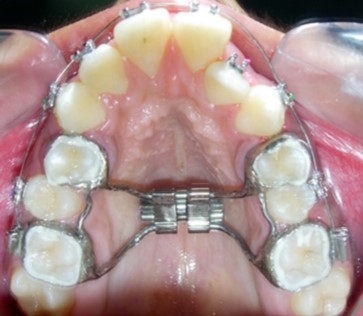

The main treatment objective was to improve the phonation, lip competence, smile esthetics and soft tissue profile. The initial phase of treatment was initiated with a banded rapid palatal expansion appliance to correct the bilateral maxillary posterior crossbite. (Figure 4). Subsequent to correction of the same, maxillary and mandibular first premolars were extracted and the orthodontic phase was commenced to correct the severe crowding of the maxillary and mandibular dental arch.

Though bonded RME could have been used, we however, preferred to use banded RME as it is more hygienic and easy to maintain with good patient co-operation.

The mandibular first premolars were first extracted to commence treatment of the mandibular arch simultaneously with expansion of the constricted maxilla. Preadjusted edgewise brackets (Roth prescription, 0.022 x 0.028-inch slot) were initially bonded to the maxillary and mandibular teeth. Banded Hyrax (Hygienic rapid palatal expander) was cemented to the maxillary first premolars and molars. (Figure 5). The patient was advised to activate the appliance a quarter turn once or twice a day to achieve adequate expansion consistently. Subsequent to over-expansion of the maxilla the Hyrax was inactivated with a ligature tie tied into the screw holes and was retained in situ for a period of 6 months, after which the maxillary first premolars were extracted and the maxillary arch treatment was commenced.

Figure 5.Rapid palatal expansion appliance in situ